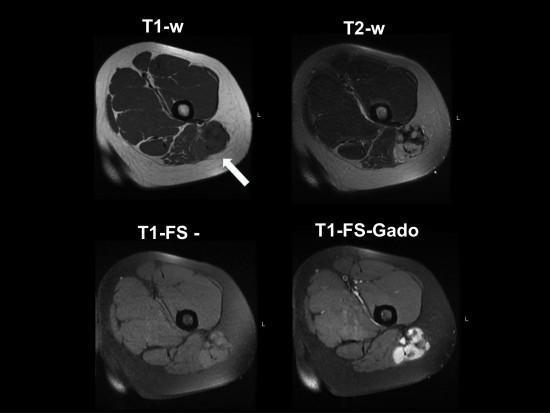

ETUDE CLINIQUE

L’étude de l’anatomie de l’artère brachial est indispensable vue la diversité de la pathologie

- Traumatique dans les lésions vasculaire de l’artère brachial et ces branches collatérales

- Infectieuse

- néoplasique dans le cas des tumeurs vasculaire

- Un intérêt sémiologique dans le cathétérisme artérielle( réanimation et imagerie)

INTERET SEMIOLOGIQUE